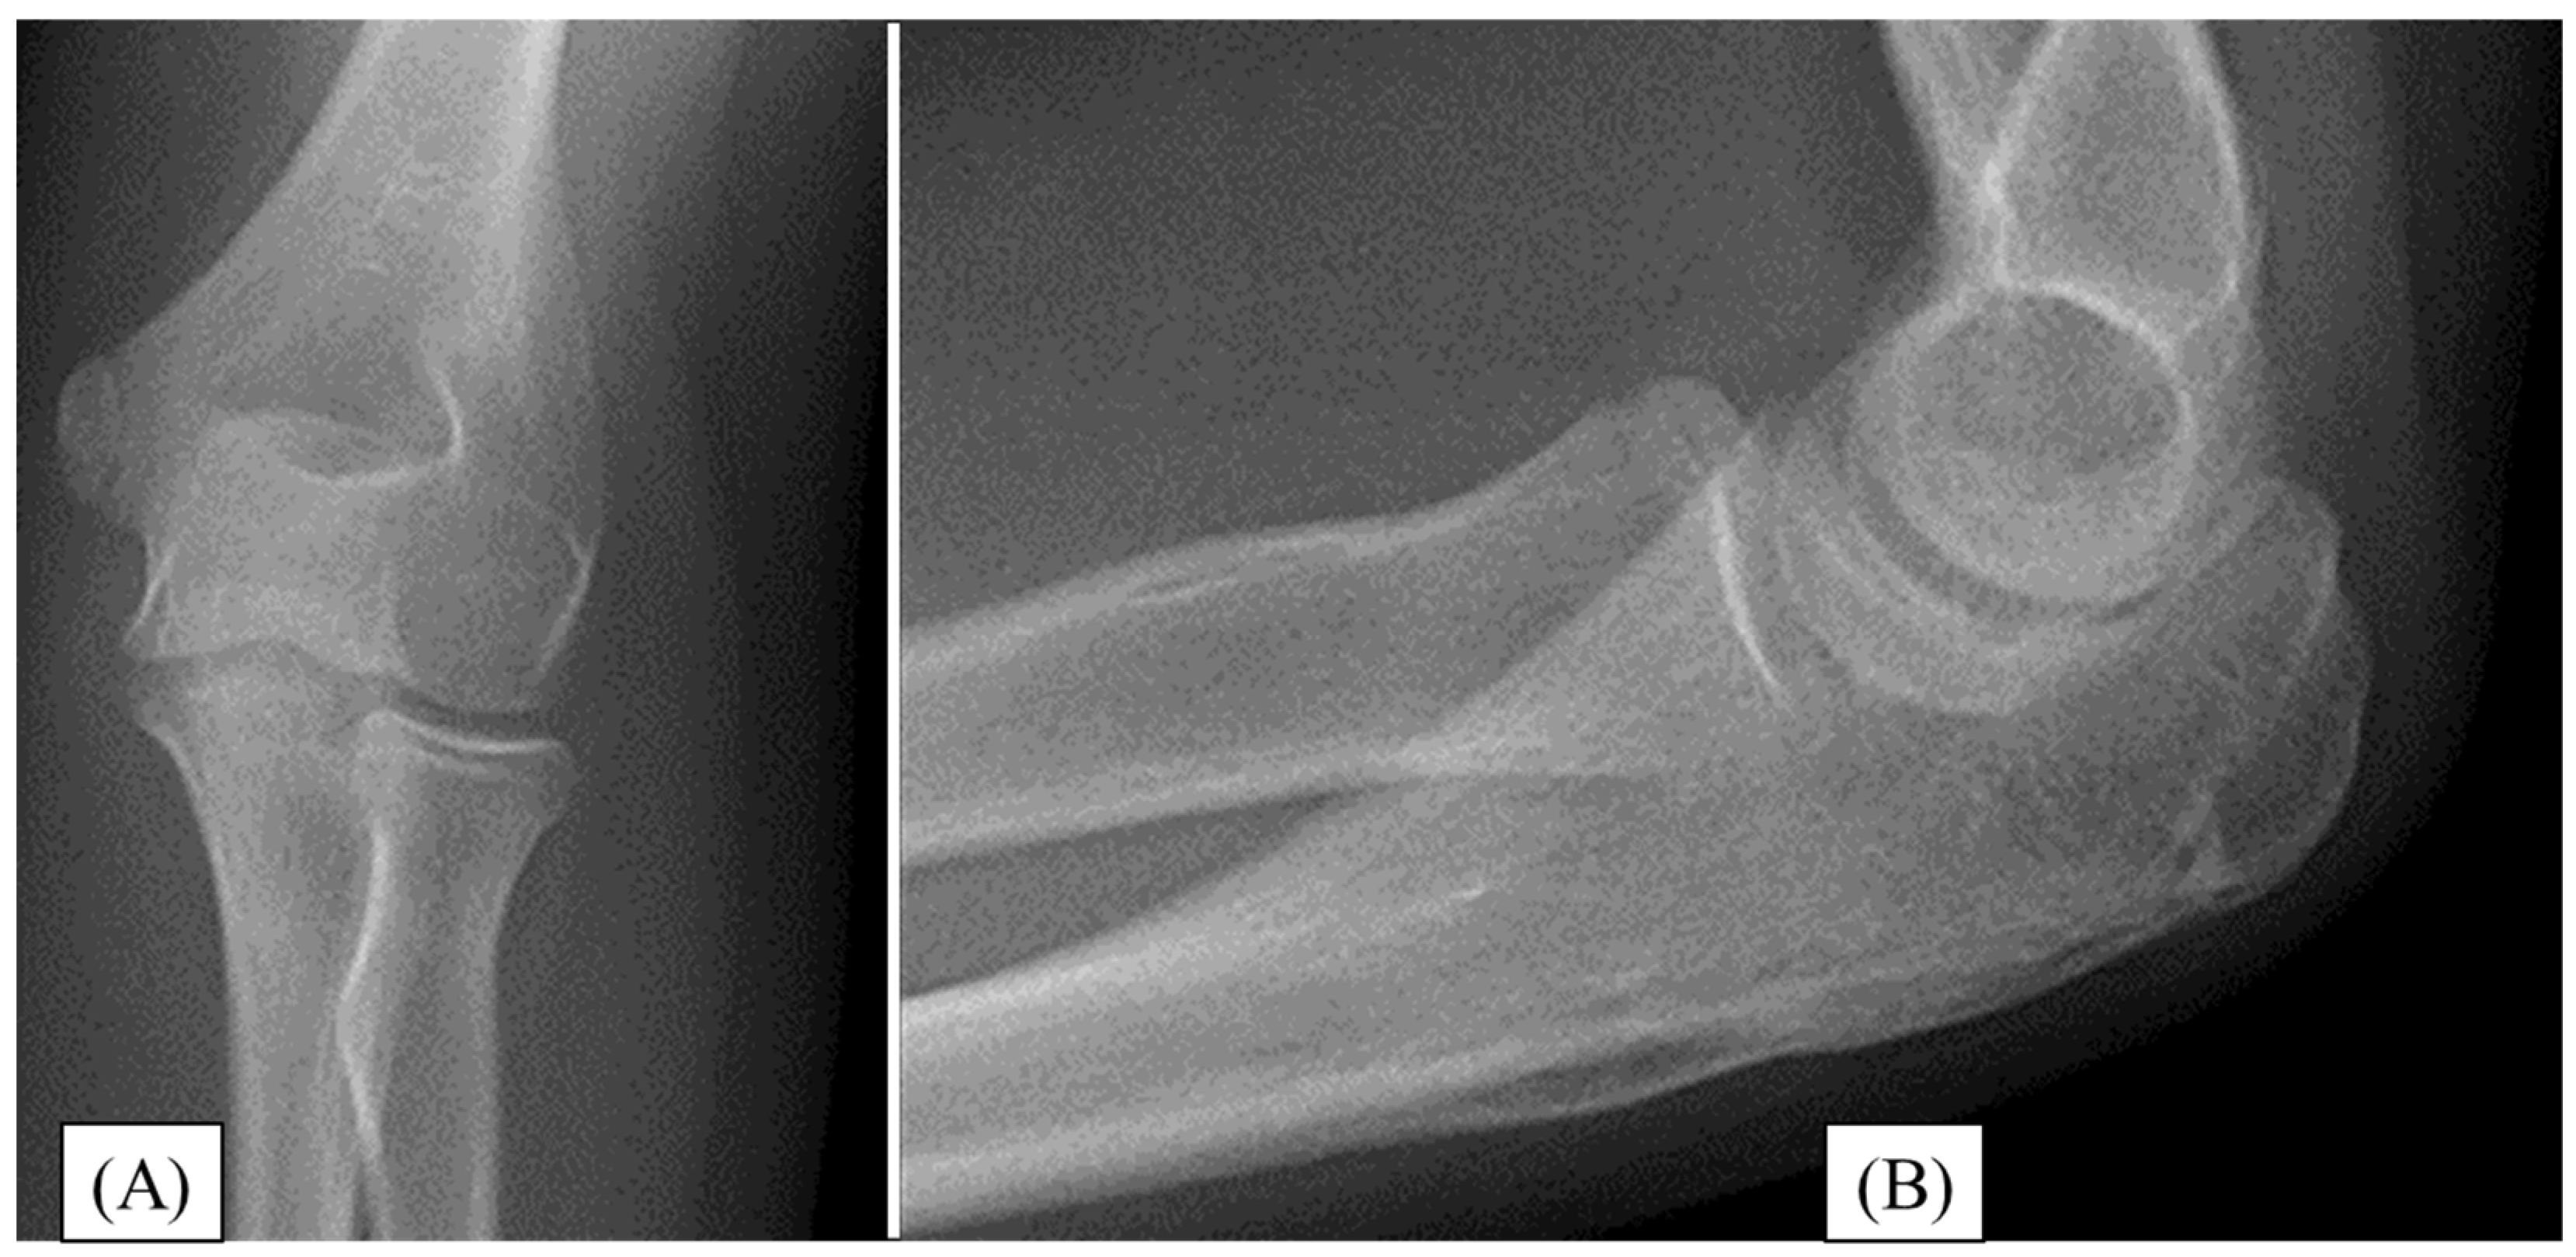

3.2. Case 2